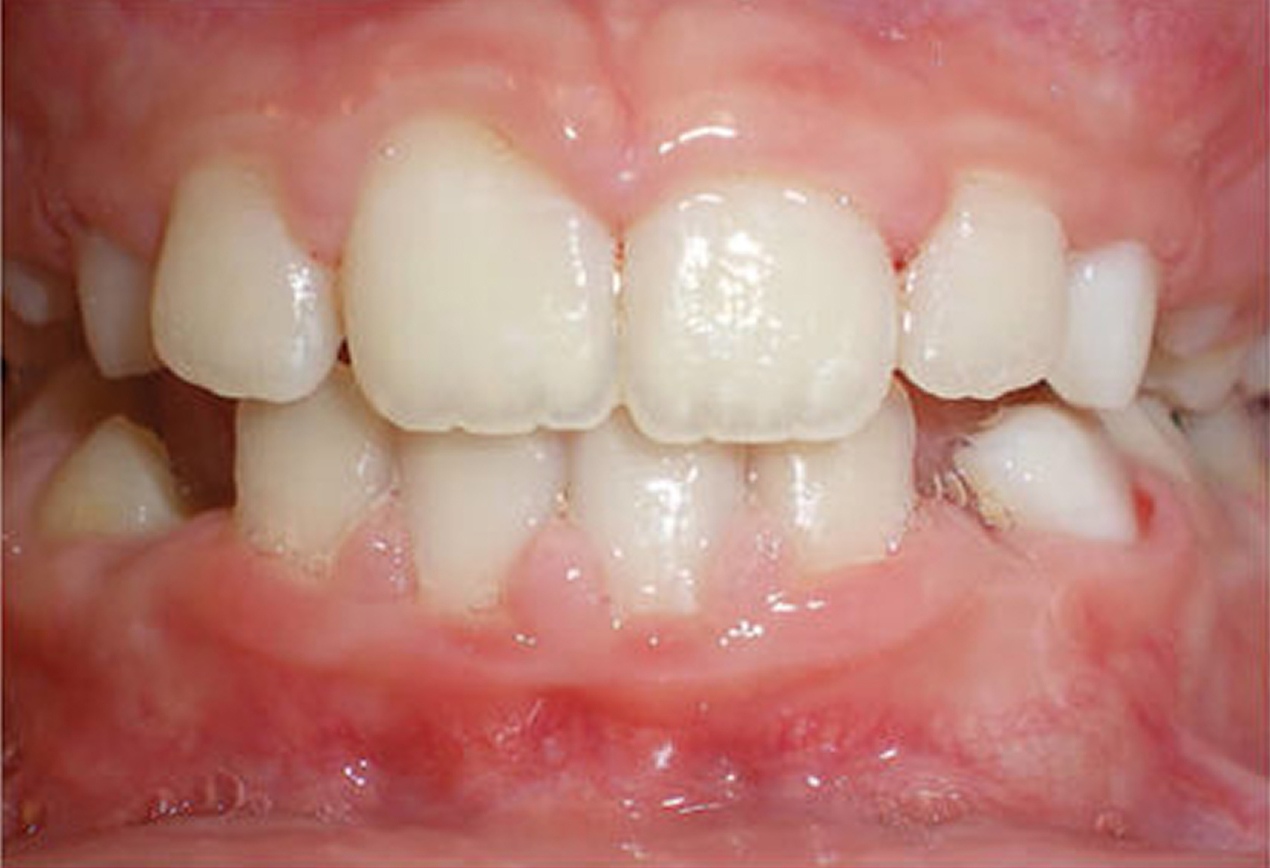

For many patients, an orthodontic intervention in Highland, NY or Ramsey, NJ can improve and sometimes eliminate these risks. Below are pictures of an OSA patient that benefitted from orthodontic treatment’s life-changing effects at Van Vliet & Ganz Orthodontics.